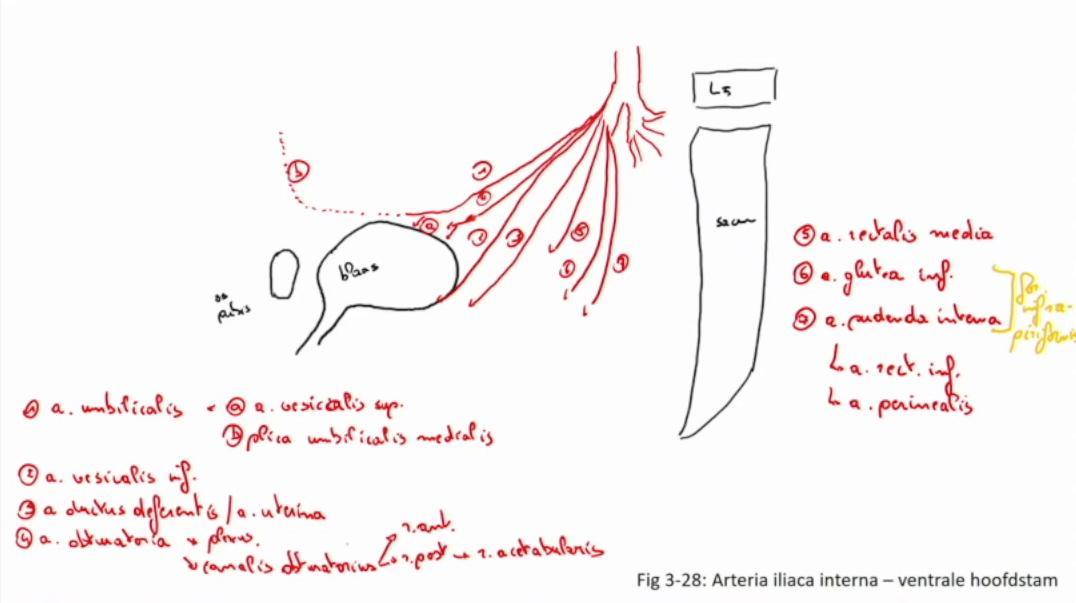

Fig 3.28: a. iliaca interna - ventrale hoofdstam

os pubis vesica urinaria (blaas) L5 sacrum -

a iliaca interna

dorsale hoofdstam -

ventrale hoofdstam

|